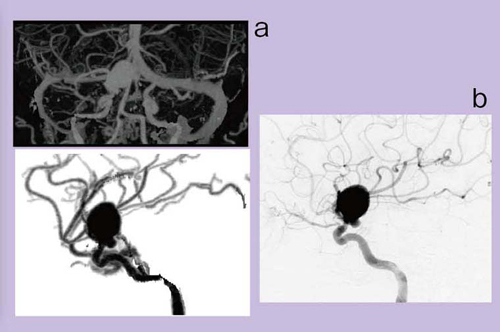

全周性に石灰化が認められるLtMCAの動脈瘤症例の場合,通常のCTAのVR画像では血管壁の石灰化は見えても内腔の評価はできない(図5)。しかし,DEイメージングで骨除去を行うと,きれいに石灰化が取れて,内腔の狭窄を評価することができるようになる(図6)。

初期の12例の結果をまとめると,骨除去の平均計算時間は55秒で,1分以内に画像が表示され,動脈瘤や石灰化動脈瘤の評価が容易になった。一方,ICA狭窄が疑われた5症例では,DSAと比べて狭窄率をやや過大評価するという傾向が見られた。

図5 Lt MCAの動脈瘤症例のCTA元画像

図6 図5のDE骨除去CTA